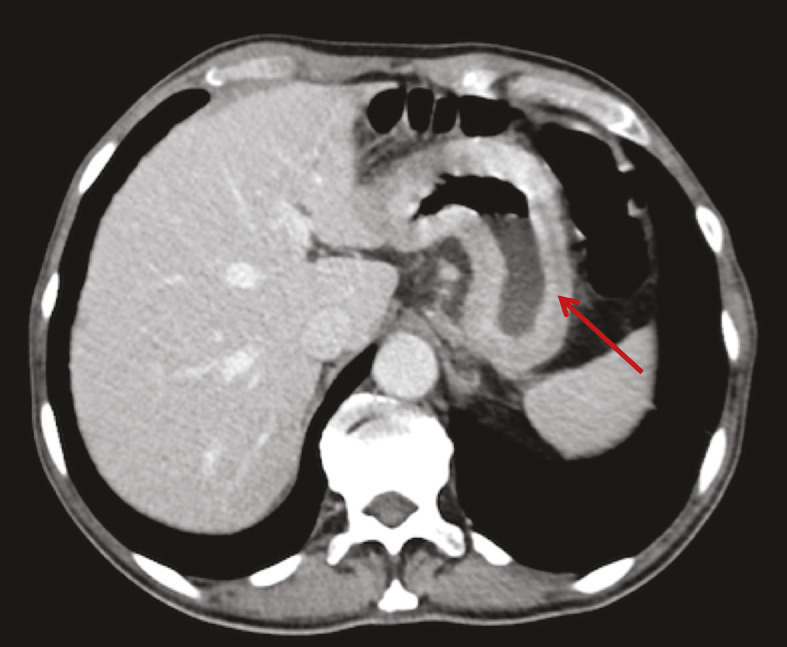

Lors du suivi, le patient revient 6 mois après la fin de son traitement adjuvant. La tomodensitométrie thoraco-abdomino-pelvienne révèle l’existence de deux lésions hépatiques hypodenses des segments VII et VIII, de 25 mm et 33 mm de plus grand axe. Une imagerie par résonance magnétique (IRM) hépatique ne montre pas d’autre lésion hépatique, et la tomographie par émission de positons au 18-fluorodésoxuglucose (TEP-TDM au 18FDG) ne révèle aucune fixation pathologique, y compris au niveau hépatique.

De même, une confusion fréquente est faite entre le type histologique ADCI et la linite gastrique. Cette dernière est définie macroscopiquement, en anatomopathologie, en endoscopie (fig. 2) ou en imagerie (fig. 3), par un aspect épaissi et rigide de la paroi gastrique. L’aspect de linite est fréquemment associé au type histologique ADCI, comme cela a été noté dans une série de 27 linites gastriques analysées par deux anatomopathologistes différents. P armi ces linites, 21 étaient des adénocarcinomes gastriques à cellules indépendantes et 6 d’autres types histologiques selon la classification de l’OMS. Après une troisième lecture des lames, il apparaissait que 4 tumeurs avaient un contingent minoritaire de cellules isolées (< 50 %) et 2 tumeurs étaient des adénocarcinomes tubulaires.3